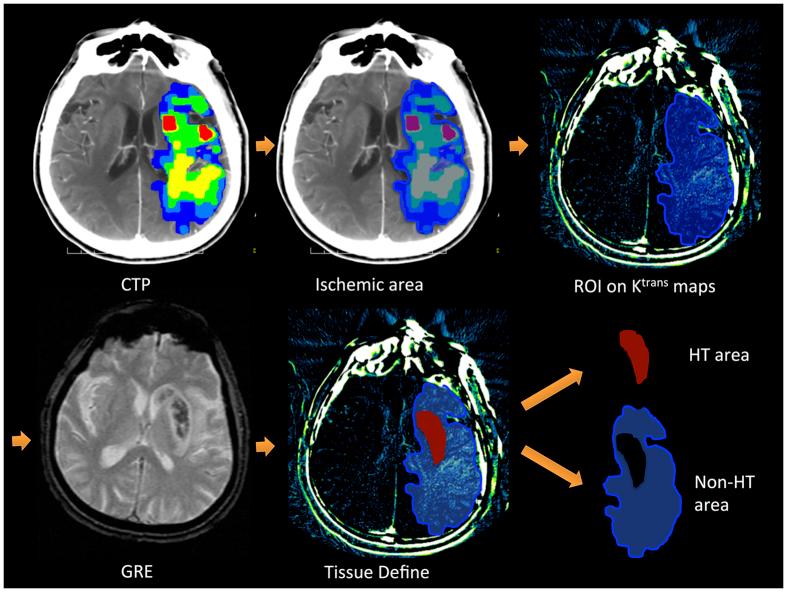

This study sought to determine whether the permeability related parameter K(trans), derived from computed tomography perfusion (CTP) imaging, can predict hemorrhagic transformation (HT) in patients with acute ischemic stroke who receive intra-arterial thrombolysis. Data from patients meeting the criterion were examined. CTP was performed and K(trans) maps were used to assess the permeability values in HT and non-HT regions. A receiver operating characteristic (ROC) curve was calculated, showing the sensitivity and specificity of K(trans) for predicting HT risk. Composite images were produced to illustrate the spatial correlations among perfusion, permeability changes and HT. This study examined 41 patients. Twenty-six patients had hemorrhagic infarction and 15 had parenchymal hemorrhage. The mean K(trans) value in HT regions was significantly lower than that in the non-HT regions (0.26 ± 0.21/min vs. 0.78 ± 0.64/min; P < 0.001). The ROC curve analysis identified an optimal cutoff value of 0.334/min for K(trans) to predict HT risk. Composite images suggested ischemic regions with low permeability, or the mismatch area of low perfusion and high permeability, more likely have HT. HT regions after intra-arterial thrombolysis had lower permeability values on K(trans) maps. The mismatch area of lower perfusion and higher permeability are more likely to develop HT.

本研究旨在确定从计算机断层扫描灌注(CTP)成像得出的与通透性相关的参数K(trans)能否预测接受动脉内溶栓治疗的急性缺血性卒中患者的出血性转化(HT)。对符合标准的患者数据进行了检查。进行了CTP检查,并使用K(trans)图评估HT区域和非HT区域的通透性值。计算了受试者工作特征(ROC)曲线,显示了K(trans)预测HT风险的敏感性和特异性。生成了复合图像以说明灌注、通透性变化和HT之间的空间相关性。本研究检查了41例患者。26例患者发生出血性梗死,15例患者发生实质内出血。HT区域的平均K(trans)值显著低于非HT区域(0.26±0.21/min对0.78±0.64/min;P<0.001)。ROC曲线分析确定K(trans)预测HT风险的最佳截断值为0.334/min。复合图像显示,通透性低的缺血区域,或灌注低与通透性高的不匹配区域,更有可能发生HT。动脉内溶栓后的HT区域在K(trans)图上的通透性值较低。灌注较低与通透性较高的不匹配区域更有可能发生HT。